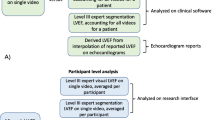

We developed a machine learning model for efficient analysis of echocardiographic image quality in hospitalized patients. This study applied a machine learning model for automated transthoracic echo (TTE) image quality scoring in three inpatient groups. Our objectives were: (1) Assess the feasibility of a machine learning model for echo image quality analysis, (2) Establish the comprehensiveness of real-world TTE reporting by clinical group, and (3) Determine the relationship between machine learning image quality and comprehensiveness of TTE reporting. A machine learning model was developed and applied to TTEs from three matched cohorts for image quality of nine standard views. Case TTEs were comprehensive studies in mechanically ventilated patients between 01/01/2010 and 12/31/2015. For each case TTE, there were two matched spontaneously breathing controls (Control 1: Inpatients scanned in the lab and Control 2: Portable studies). We report the overall mean maximum and view specific quality scores for each TTE. The comprehensiveness of an echo report was calculated as the documented proportion of 12 standard parameters. An inverse probability weighted regression model was fit to determine the relationship between machine learning quality score and the completeness of a TTE report. 175 mechanically ventilated TTEs were included with 350 non-intubated samples (175 Control 1: Lab and 175 Control 2: Portable). In total, the machine learning model analyzed 14,086 echo video clips for quality. The overall accuracy of the model with regard to the expert ground truth for the view classification was 87.0%. The overall mean maximum quality score was lower for mechanically ventilated TTEs (0.55 [95% CI 0.54, 0.56]) versus 0.61 (95% CI 0.59, 0.62) for Control 1: Lab and 0.64 (95% CI 0.63, 0.66) for Control 2: Portable; p = 0.002. Furthermore, mechanically ventilated TTE reports were the least comprehensive, with fewer reported parameters. The regression model demonstrated the correlation of echo image quality and completeness of TTE reporting regardless of the clinical group. Mechanically ventilated TTEs were of inferior quality and clinical utility compared to spontaneously breathing controls and machine learning derived image quality correlates with completeness of TTE reporting regardless of the clinical group.